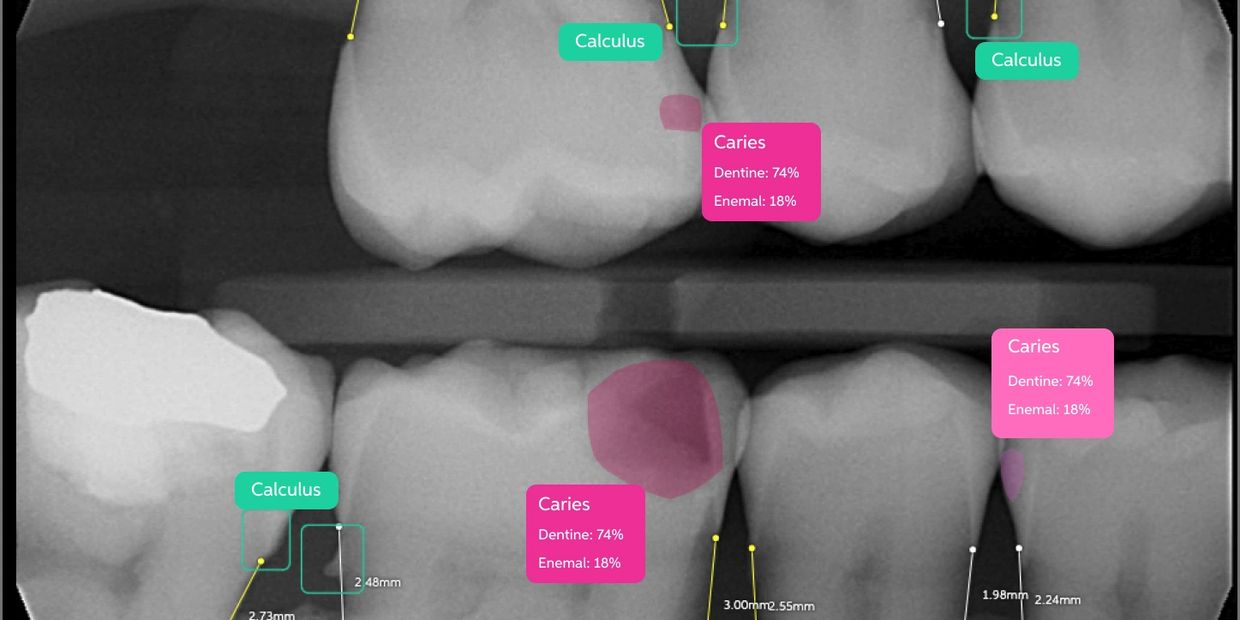

At Platypus Dental, we are committed to staying at the forefront of dental innovation. As a leading Brisbane dentist, we incorporate the latest advancements in AI dentistry to enhance the accuracy, efficiency, and comfort of your dental care. One of the most exciting tools we use is Dentally AI, a cutting-edge program designed to revolutionize diagnostics and treatment planning.

Artificial intelligence in dentistry leverages powerful algorithms to assist in diagnosing dental issues, improving treatment precision, and optimizing patient care. AI technology analyzes vast amounts of data with incredible accuracy, allowing our Brisbane dentists to detect issues such as cavities, gum disease and periapical diseases.